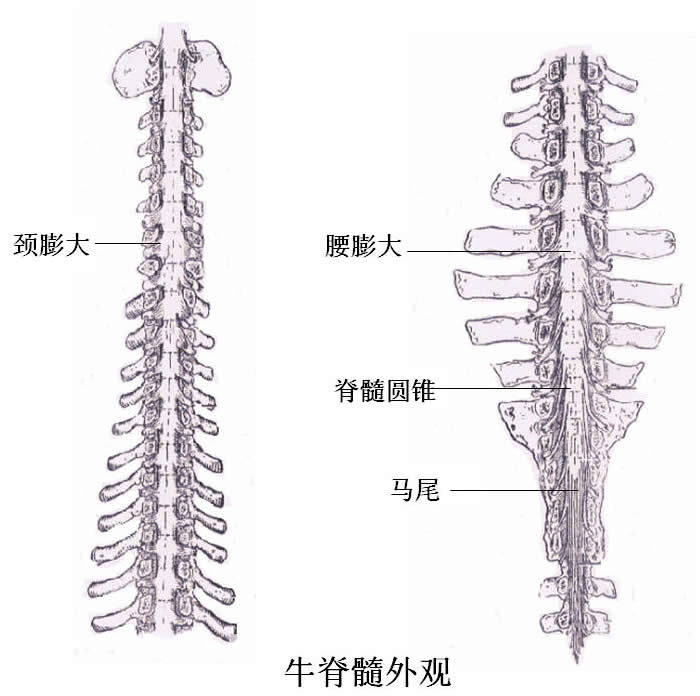

3.2 脊髓

中枢神经系统的低级部位,位于椎管内,前端枕骨大孔与脑相接,外连周围神经,31对脊神经分布于它的两侧,后端达盆骨中部。

脊髓的功能有以下两个方面:

(1)传导功能

全身(除头外)深、浅部的感觉以及大部分内脏器官的感觉,都要通过脊髓白质才能传导到脑,产生感觉。而脑对躯干,四肢横纹肌的运动调节以及部分内脏器官的支配调节,也要通过脊髓白质的传导才能实现。若脊髓受损伤时,其上传下达功能便发生障碍,引起感觉障碍和瘫痪。

(2)反射功能:

脊髓灰质中有许多低级反射中枢,可完成某些基本的反射活动;如肌肉的牵张反射中枢,排尿排粪中枢、性功能活动的低级反射中枢,跖反射、膝跳反射和内脏反射等躯体反射。